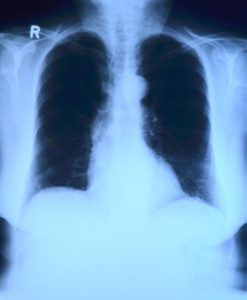

Røntgenundersøgelse